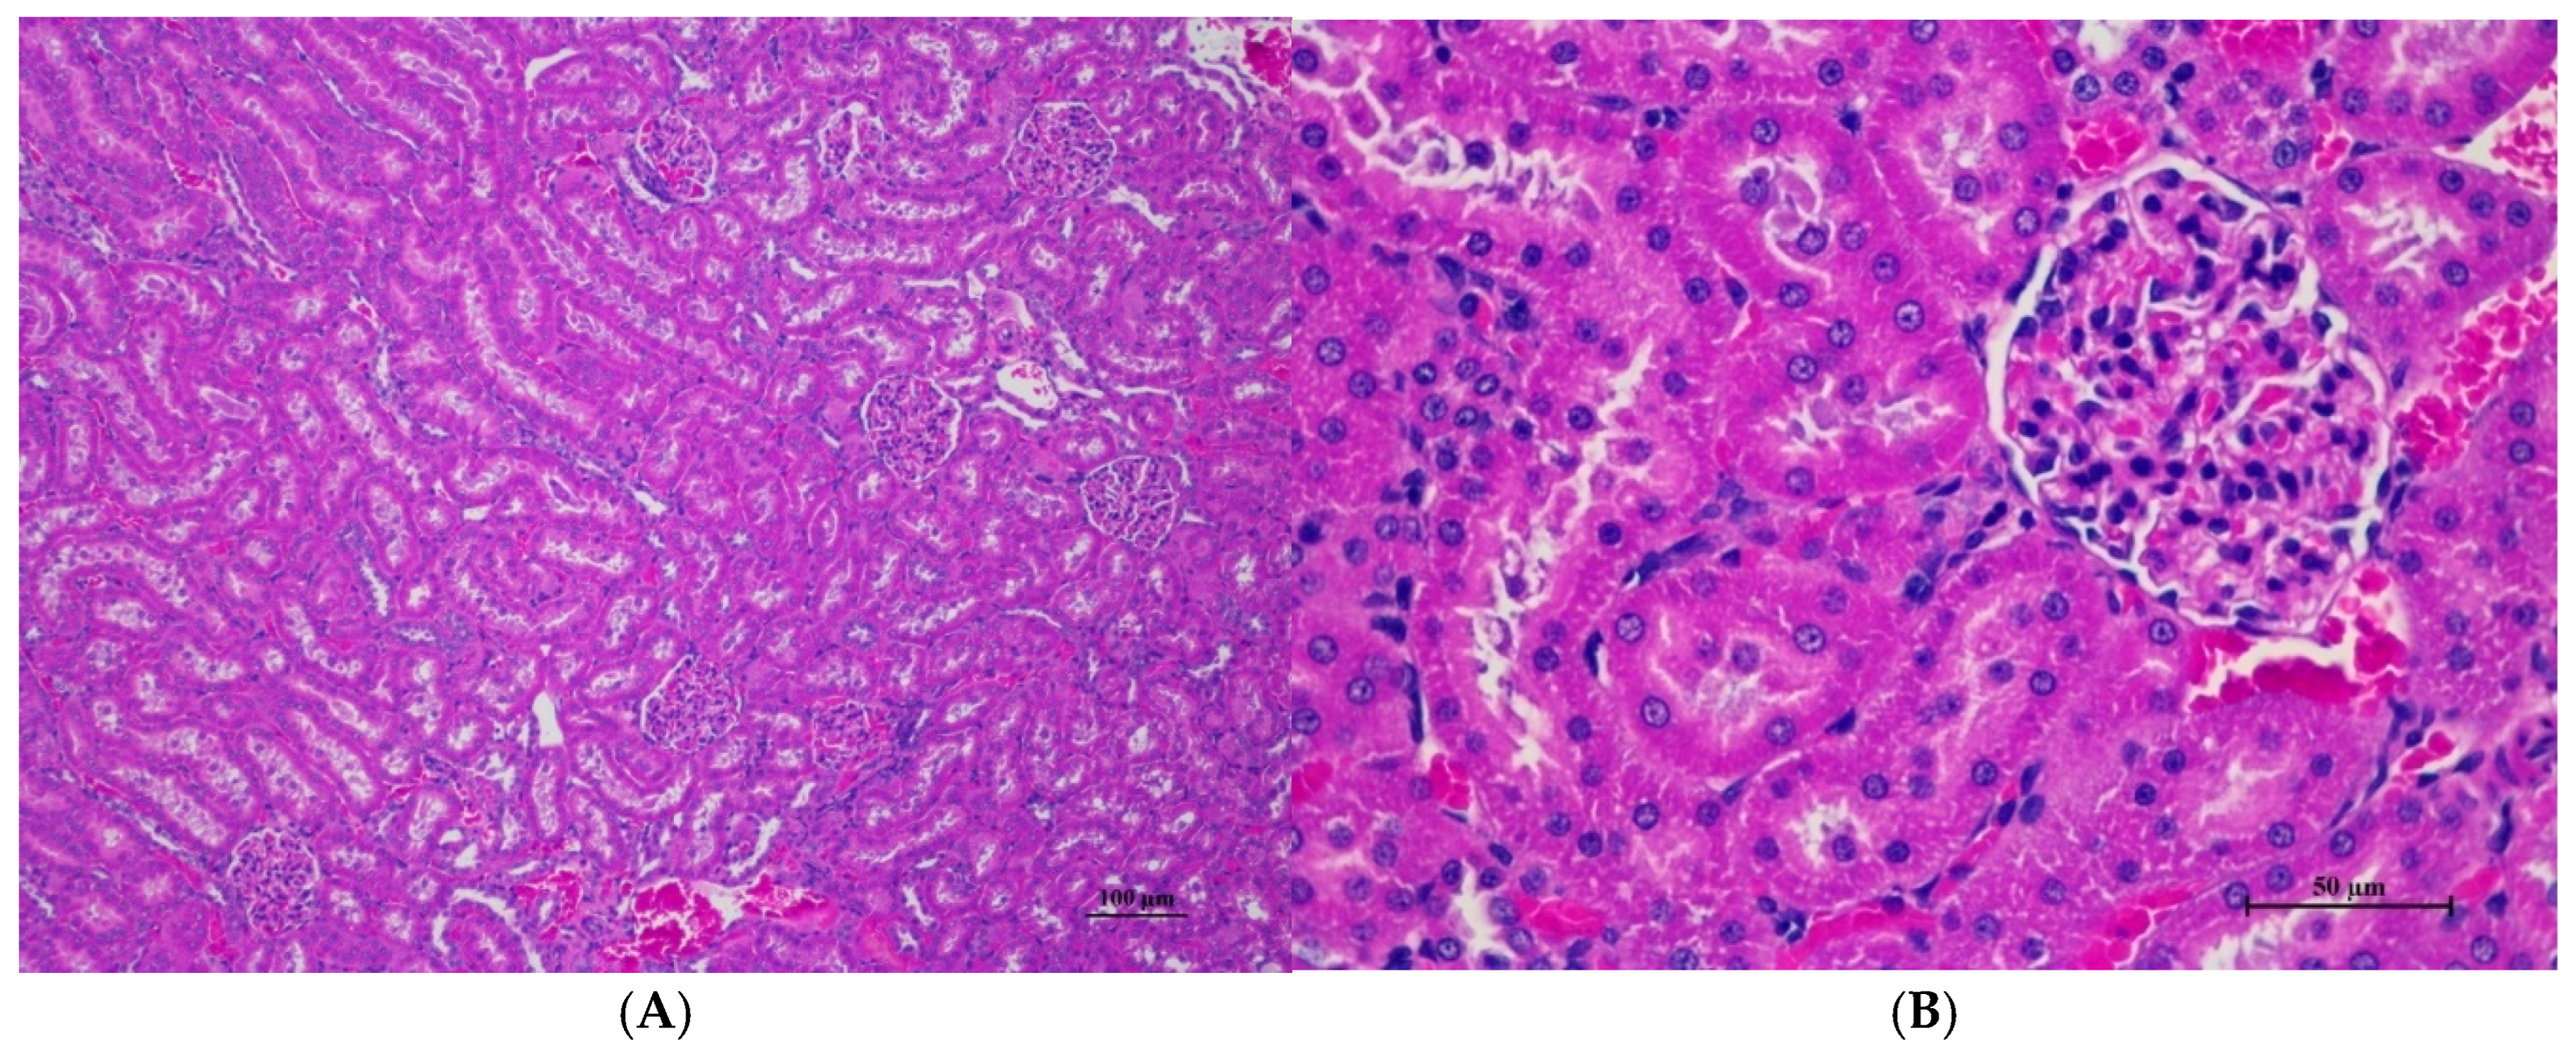

Figure 2.

Histopathological examination of rat renal tissue in acute toxicity from a single oral dose of CDF revealed well-preserved histological structure. (A) The renal tissue showed a normal histologic appearance with intact glomeruli and tubular structure (100×, H&E). (B) High magnification displayed uniform renal tubule with normal glomeruli. Mild cytoplasmic change with no evidence of inflammation, cell death, or necrosis observed (400×, H&E).

Histopathological analysis revealed generally unremarkable findings in the liver, kidney, heart, and spleen, with only minor, scattered hepatocellular swelling and vacuolation in the liver, mild renal tubular degeneration in limited kidney areas, and focal myocardial vacuolation and lymphoid aggregation in the heart. Conversely, the lung exhibited significant pathological changes, characterized by alveolar septal thickening due to severe interstitial infiltration of lymphocytes and other mononuclear cells, nodular lymphoid aggregations, alveolar septal engorgement and hyperemia, alveolar edema, and multifocal mild alveolar hemorrhage, suggesting a potential site of inflammatory response.